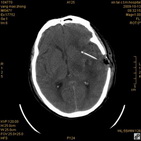

病人杨XX,男,青云街道办事处路踏泉村,住院号51666,CT号:104770。病人因“高血压脑出血”在新泰市人民医院住院治疗5天,治疗效果不佳转入我院,复查CT示左基底节血肿,病人昏迷状态,给予血肿清除术,术后2天复查CT,血肿完全清除,病人恢复好,治疗效果满意。附病人术前术后CT片资料如下。

术后46小时复查CT

术后46小时复查1 术后46小时复查2 术后46小时复查3 术后46小时复查4